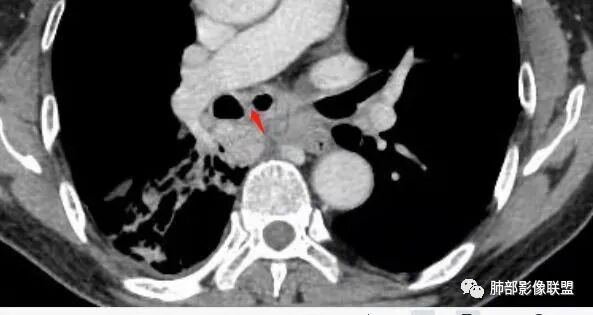

气管隆突下团片影,其内积气,与食道分界不清,食道壁增厚,管腔狭窄,右下肺实变影,支气管壁增厚,考虑食管支气管瘘并右下肺感染,食道肿瘤病变不除外

支持食管支气管瘘(考虑食管癌)伴后纵隔及右肺感染,食管管壁明显增厚,管腔狭窄,相邻右侧后纵隔内软组织内可见气体影,与食管分界不清,右肺有实变及不张。

右肺下叶沿肺叶肺段分布斑片、条片状影,以下叶背段为显,边缘模糊,内可见支气管走行,局部支气管管壁增厚,右侧胸腔少量积液。纵隔隆突下可见不均匀软组织密度影,与周围结构分界不清,内见气体密度影,与食管及相邻右肺支气管之间未显示通道。邻近食管下段壁明显不规则增厚,增强后食管管壁明显不均匀强化,可见线样强化的连续完整粘膜影。

右肺下叶片影,气道相关,符合感染性病变。纵隔隆突下软组织密度影,异常气体影,长病程,起病缓慢,提示存在气管或食管瘘。食管镜未见明显新生物形成,临床未提供进食或饮水呛咳临床表现,综合分析应该考虑支气管瘘的形成。

对比患者3月份的CT图,原隆突下存在增大钙化淋巴结,现在出现气体影,且钙化显示不清,应想到淋巴结结核破溃成瘘可能性。